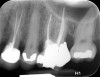

Clinical procedure: Regeneration of the endodontic pulp space is indicated for cases with very thin dentinal walls and an open apex that is more than 1 mm in diameter radiographically (Figure 4). Disinfection of the root canal system is performed using sodium hypochlorite irrigation followed by a triple antibiotic paste dressing that is left in place for 1 week. At the second visit, ethylenediaminetetraacetic acid (EDTA) is used to condition the dentin walls, which results in the release of growth factors, and bleeding is stimulated in the periapical tissues (where stem cells are located), with the aim of filling the pulp space with a stable blood clot, which would serve as the scaffold. MTA is then placed at the canal orifice in contact with the clot to protect it from coronal microleakage (Figure 5 and Figure 6). In time, the clot should be replaced with a reparative tissue of variable composition, and the root walls should continue to thicken due to the deposition of a dentin-like material on the pre-existing root dentin27,28 (Figure 7 and Figure 8).